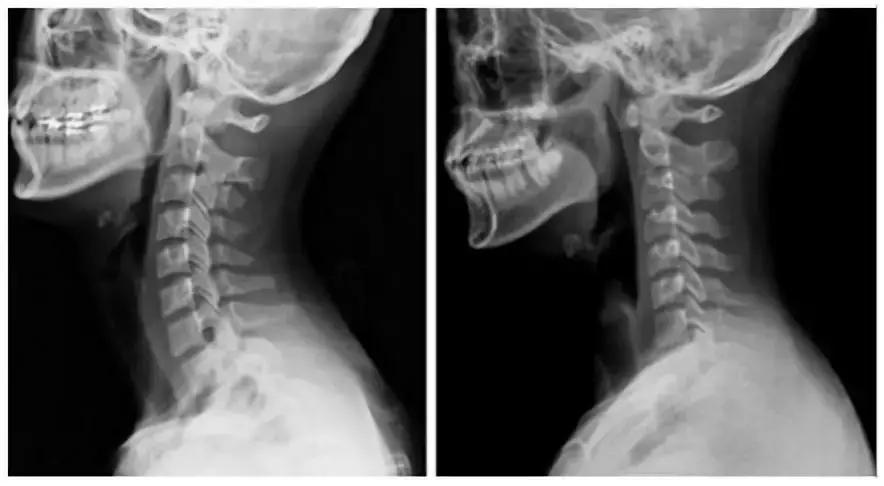

现在的办公室人群甚至连小学生,也常常会出现颈椎不适的症状,到医院检查往往会得到颈椎生理曲度变直、反弓的结论。

颈椎的生理曲度(简称颈曲)并非是一成不变的,随着年龄的增长颈椎会出现退行性改变,而使颈曲发生改变,甚至使颈曲变直或反张弯曲。

但是现在的年轻人出现颈椎生理曲度变直甚至反弓主要是因为长期姿势不当、生活习惯不良:比如长时间低头工作、睡高枕等原因。

颈曲的改变或消失,往往意味着椎体稳定性变差,椎间隙变窄,椎间孔变小,椎体退变,周围韧带肌肉慢性损伤,这会成为各种颈椎病如韧带增生、钙化、颈椎间盘突出、椎动脉狭窄等的结构和病理基础。